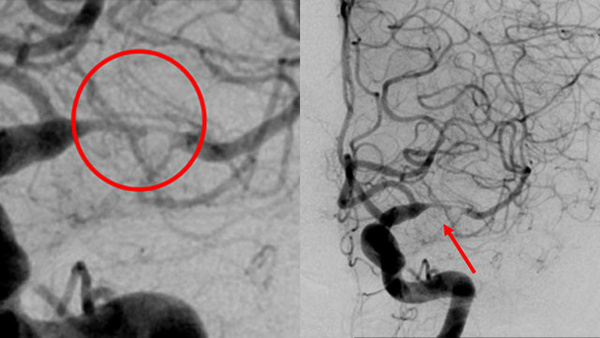

Dive into a curated collection of compelling clinical cases shared by leading experts from LINNC Paris, LINNC Seminars, and LINNC online. Discover a diverse array of complex cases, including aneurysm embolization, AVM/fistula management, stroke interventions, and cSDH treatment. Each case study provides an in-depth exploration of advanced procedures, innovative techniques, and their real-world applications in diagnosing and managing neurovascular conditions.

EVT For Ruptured PICA Aneurysm

AneurysmsStent assisted coiling